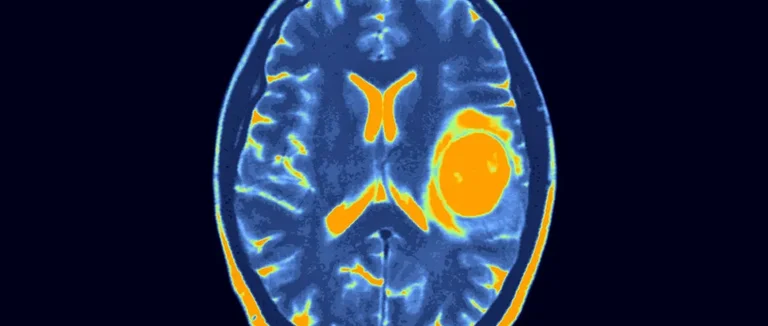

Capacité des CT Scans à Détecter les Tumeurs Cérébrales

Les CT scans peuvent détecter certaines tumeurs cérébrales. Mais, ils ont des limites dans leur précision diagnostique.

Types de Tumeurs Facilement Détectables

Les CT scans sont bons pour les tumeurs de grande taille. Ils sont aussi utiles pour les tumeurs avec des caractéristiques uniques comme des calcifications. Les tumeurs malignes grandes sont souvent plus faciles à voir grâce à leur taille et leur impact sur les alentours.

Les méningiomes, gliomes de haut grade et métastases cérébrales sont souvent visibles. Ces tumeurs sont plus visibles en raison de leur taille, de leur emplacement ou de leur contraste avec les tissus cérébraux.

Précision Diagnostique des CT Scans

La précision des CT scans pour les tumeurs cérébrales dépend de plusieurs facteurs. La taille, l'emplacement de la tumeur et la qualité de l'équipement sont importants. Les CT scans modernes avec des détecteurs multiples offrent une meilleure résolution et une plus grande précision.

Utiliser un produit de contraste lors d'un CT scan peut changer beaucoup. Ce produit aide à voir mieux certaines zones du corps. C'est très utile pour détecter les tumeurs cérébrales.

Amélioration de la Visualisation grâce au Produit de Contraste

Le produit de contraste rend les tumeurs cérébrales plus visibles. Il augmente le contraste entre les différentes parties du cerveau. Ainsi, les radiologues peuvent mieux voir les tumeurs par rapport aux tissus sains.